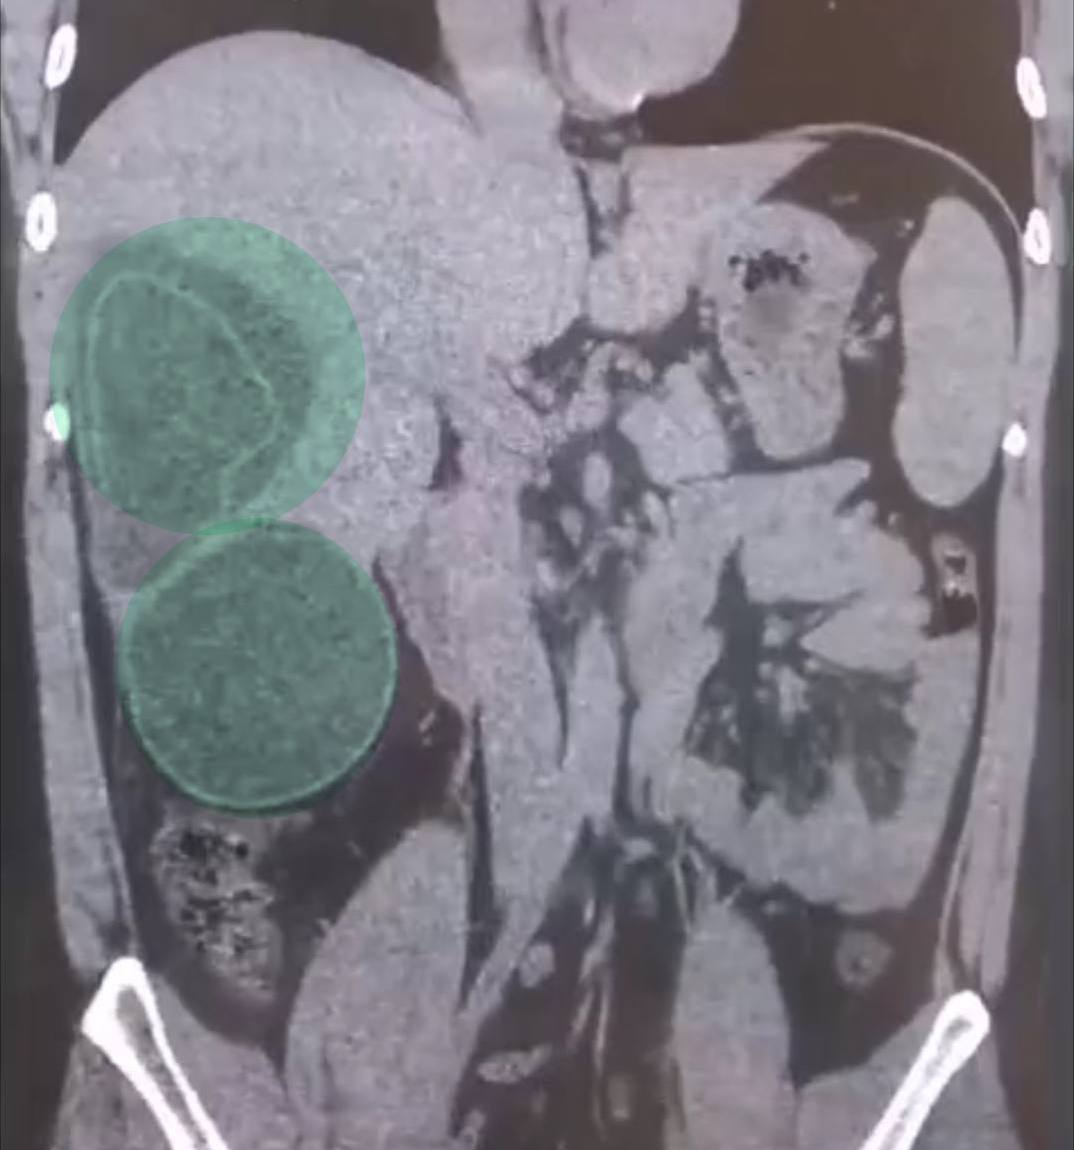

После возвращения из путешествия его состояние ухудшилось. Врачи обнаружили в организме 3 кисты с ленточными червями.

Кисты уже почти достигли максимального размера.